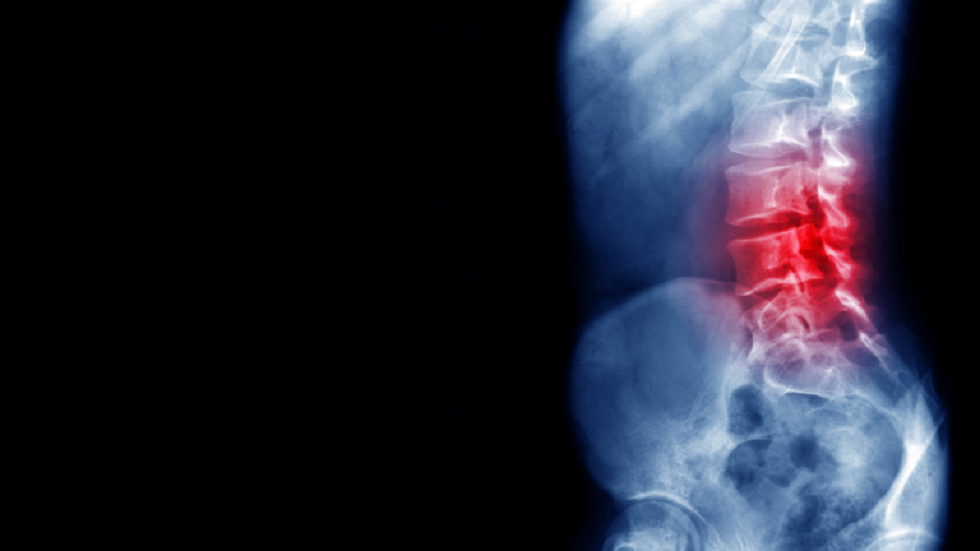

ومرض الفقار القسطي، هو نوع من أنواع التهاب المفاصل، ولكنه يصيب فقرات العمود الفقري أسفل الظهر ومنطقة الحوض، ما يسبب ألما شديدا ويمكن أن يؤدي إلى الإعاقة. وهو من أمراض المناعة الذاتية. أي ينجم عن مهاجمة خلايا منظومة المناعة عن طريق الخطأ للنسيج الضام في المفاصل والأربطة بالجسم. والأدوية المستخدمة حاليا تخفف الأعراض فقط لكنها لا تعالج المرض.